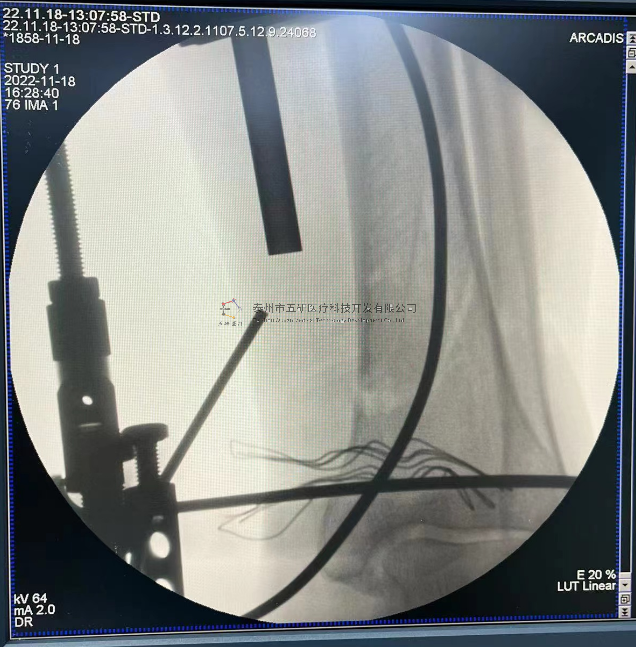

// 踝關(guān)節(jié)

本病例由中國中醫(yī)科學(xué)院望京醫(yī)院骨關(guān)二提供(術(shù)者:支架主任蔣主任)

【基本資料】患者,男,41歲

本病例踝關(guān)節(jié)骨折。手術(shù)名稱:左踝關(guān)節(jié)骨折外固定支架手術(shù)

【治療后影像】

【手術(shù)資料】